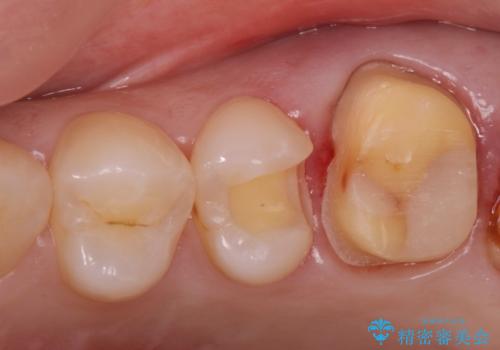

- 銀が目立つので白くしたいとの事で来院。

銀の詰め物を拡大鏡下で取り除き、う蝕がないことを確認してから

ZrCrの被せ物で治療を行いました。

また、一つ手前の歯に小さな虫歯があったため

e-maxインレーでの治療を行いました。